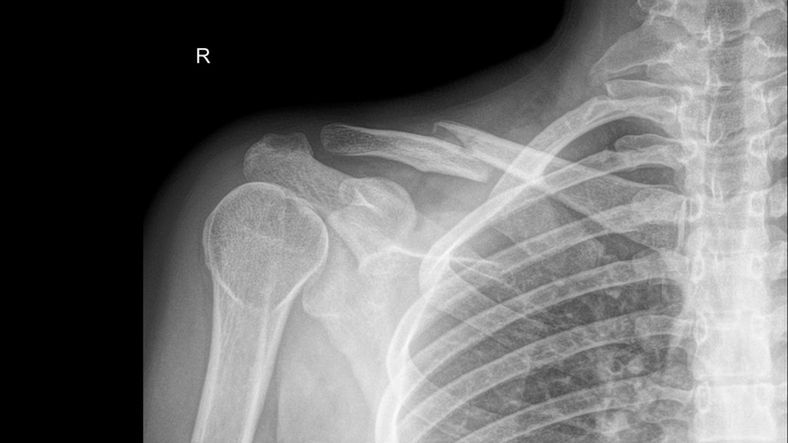

Obojczyk pozornie nie wydaje się być szczególnie powiązany z brzuchem, ale ból tej kości łączącej łopatkę z mostkiem może świadczyć o problemach z żołądkiem. To ważny sygnał wysyłany przez organizm, którego nie należy bagatelizować.

Ból obojczyka może świadczyć o tym, że w żołądku rozwijają się wrzodyBól obojczyka może świadczyć o tym, że w żołądku rozwijają się wrzody

Choć ból obojczyka może sugerować wrzody żołądka, istnieje wiele innych przyczyn dolegliwości. Nieodpowiednia pozycja do spania lub urazy i kontuzje to najbardziej oczywiste źródła bólu w okolicach obojczyka.